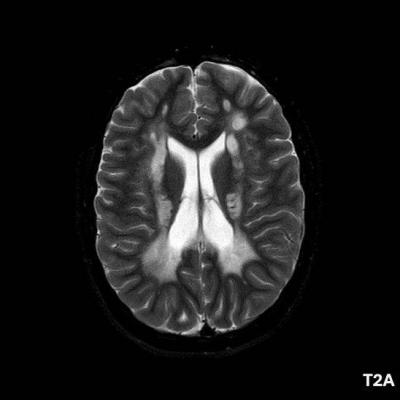

- A) Aksiyel T2A ve koronal T2A sekanslarda sentrum semiovale, korona radiata ve bazal ganglionlar düzeyinde bilateral frontoparietal derin periventriküler beyaz cevherde birleşme eğilimi gösteren hiperintens gliotik sinyal değişiklikleri (oklar) ve aksiyel T2A serilerde servikal spinal kordda posterior kolonda, lateral kesimlerde sinyal artımları (oklar) izlendi.

- LBSL, karakteristik radyolojik özelliklere sahiptir. MRG’de tipik olarak bilateral ve simetrik beyaz cevher sinyal değişiklikleri görülürken, subkortikal U lifleri, internal kapsülün posterior kolları, trigeminal sinir traktları, serebellum, korpus kallozumun spleniumu, medulla oblongata ve omurilikteki dorsal kolonlar ile lateral kortikospinal traktlar genellikle korunur.

- Etkilenen bölgelerde T1’de hipointens, T2/FLAIR’da hiperintens sinyal değişiklikleri izlenir. DWI’de lezyonların periferinde kısıtlı difüzyon görülebilir. MRS’de beyaz cevherde laktat artışı saptanabilir, ancak bu her hastada mevcut değildir.

- LBSL tanısında majör kriterler; subkortikal U lifleri korunmuş serebral beyaz cevher, servikal düzey dahil omurilik dorsal kolonları ve lateral kortikospinal traktlar, medulla oblongata piramitleri veya medial lemniskus dekusasyonu tutulumu iken; minör kriterler korpus kallozum spleniumu, internal kapsül posterior kolu, superior ve inferior serebellar pedinküller, trigeminal sinir traktları, mezensefalik trigeminal yollar, medulla oblongata anterior spinosebellar traktları ve serebellar beyaz cevherdeki sinyal değişiklikleridir.